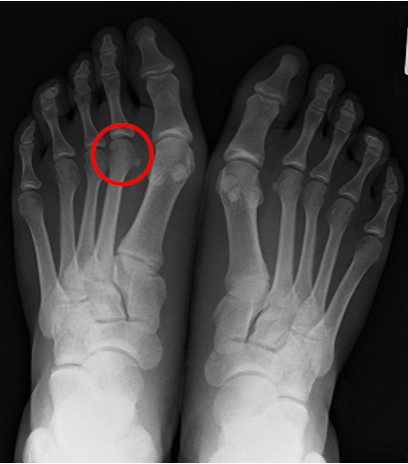

レントゲン画像による診断

レントゲンでは、骨の状態を確認し、

骨頭が変形していないかを確認します。

左のレントゲン画像は、StageⅡのレントゲン画像であり、

赤丸印の第2中足骨頭の扁平化が見られます。